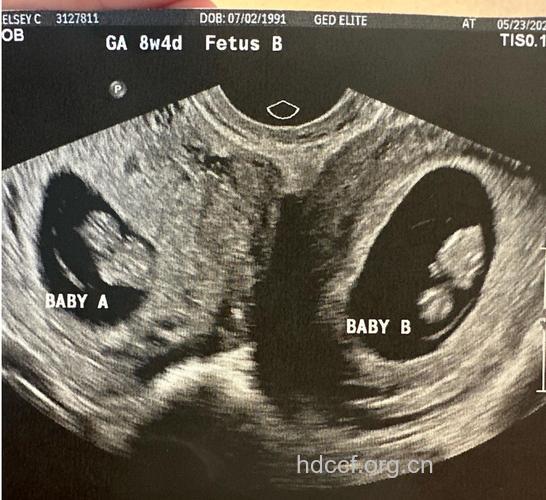

3、在流产前作B超检查,则可查看胎囊的大小,以估计妊娠天数的多少,还可发现是否异常妊娠,是否适用于做药流。